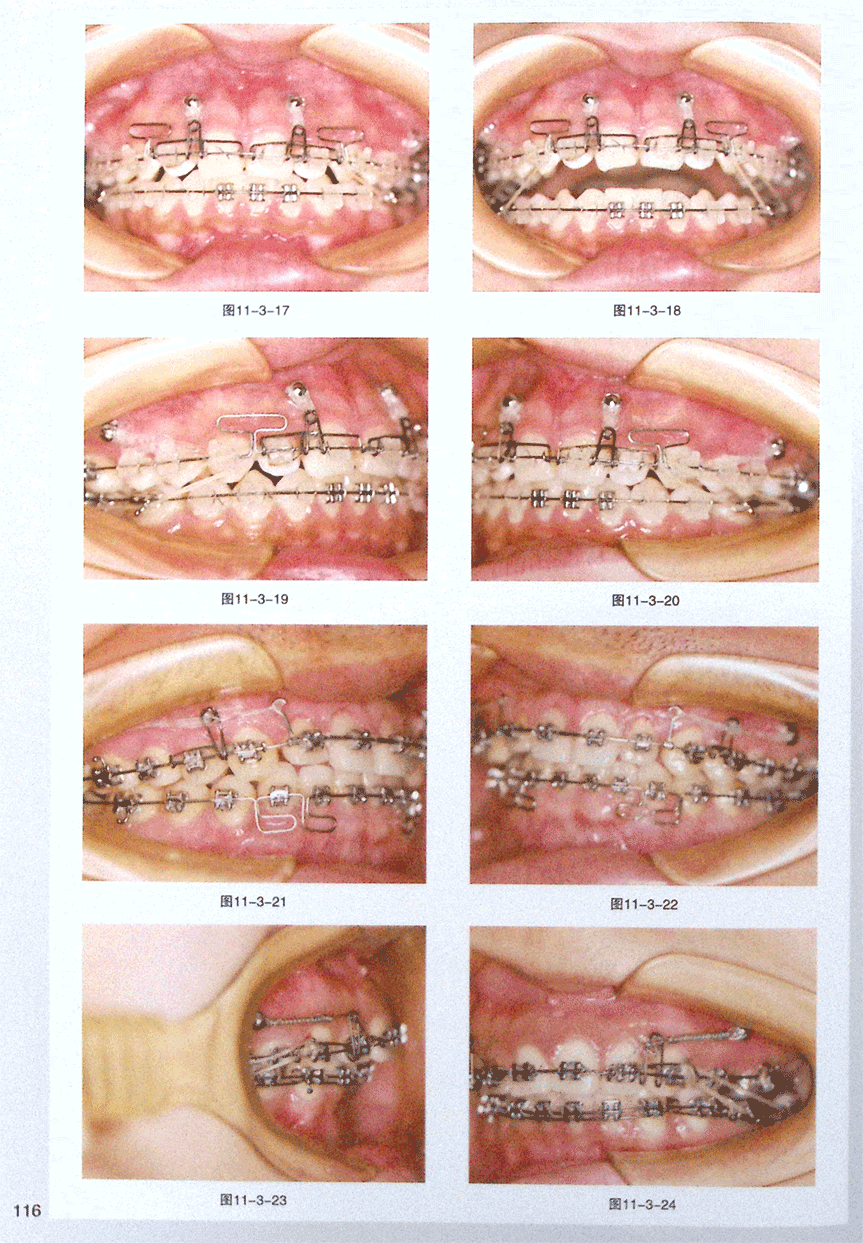

第三节 种植钉牵引支架“小蜜蜂”装配步骤